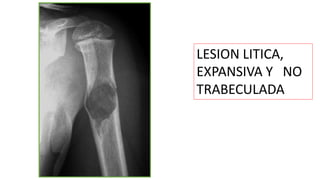

LESION LITICA,

EXPANSIVA Y NO

TRABECULADA

Lesión líticaen metáfisis del peroné,

unilocular,en relacióncon QOS de

localización nohabitual